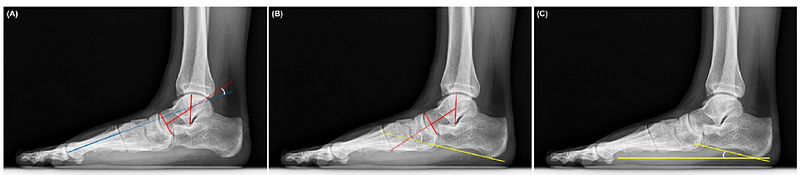

체중 부하 측면 방사선 사진(WBLR)은 성인 편평족 변형 진단의 표준 검사법으로 여겨집니다. 진단을 위해 여러 각도를 측정하는데, 주요 각도로는 거골-첫 중족골 각도(TMA), 거골-종골 각도(TCA), 종골 경사각(CPA)이 있습니다.

1*VgB0YJnpoy7s6FrYIU-fhQ.png Figure 1. 표준 체중 부하 측면 방사선 각도 측정 시연. (A) 거골-첫 중족골 각도. (B) 거골-종골 각도. (C) 종골 경사각.